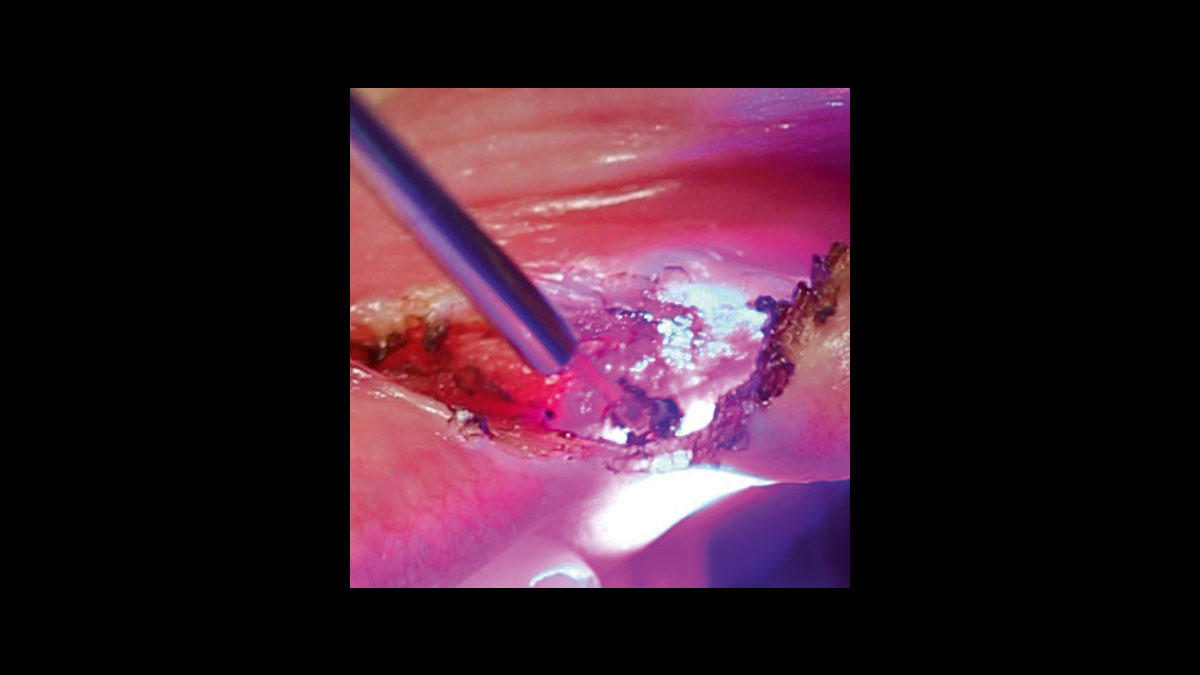

• Épulis

Fibroma